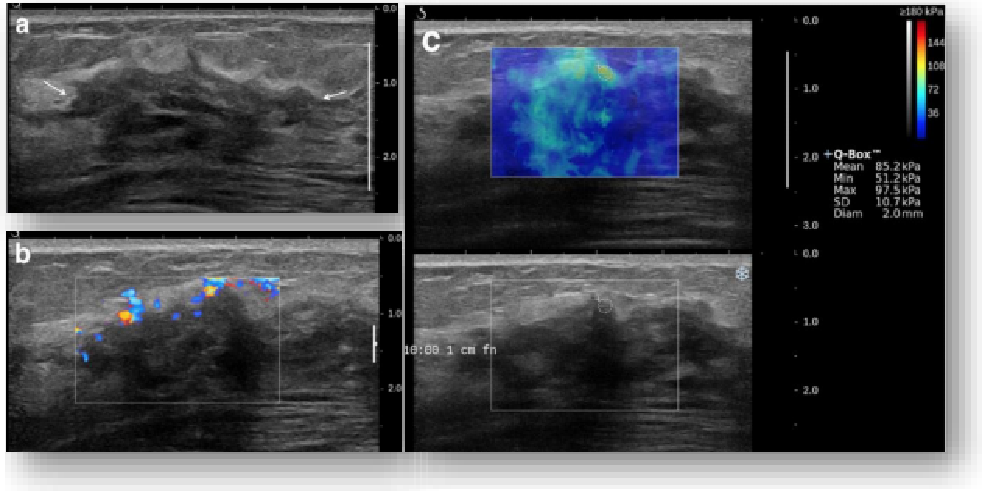

image.png

左图病例所示:

钼靶阴性,B型发现非肿块病变

剪切波弹性成像见明确的硬度增高区域。

穿刺及手术病理结果:浸润性导管癌(IDC)

非肿块型病变:B型图像无法确认病变范围,E成像帮助发现异常区域和评估